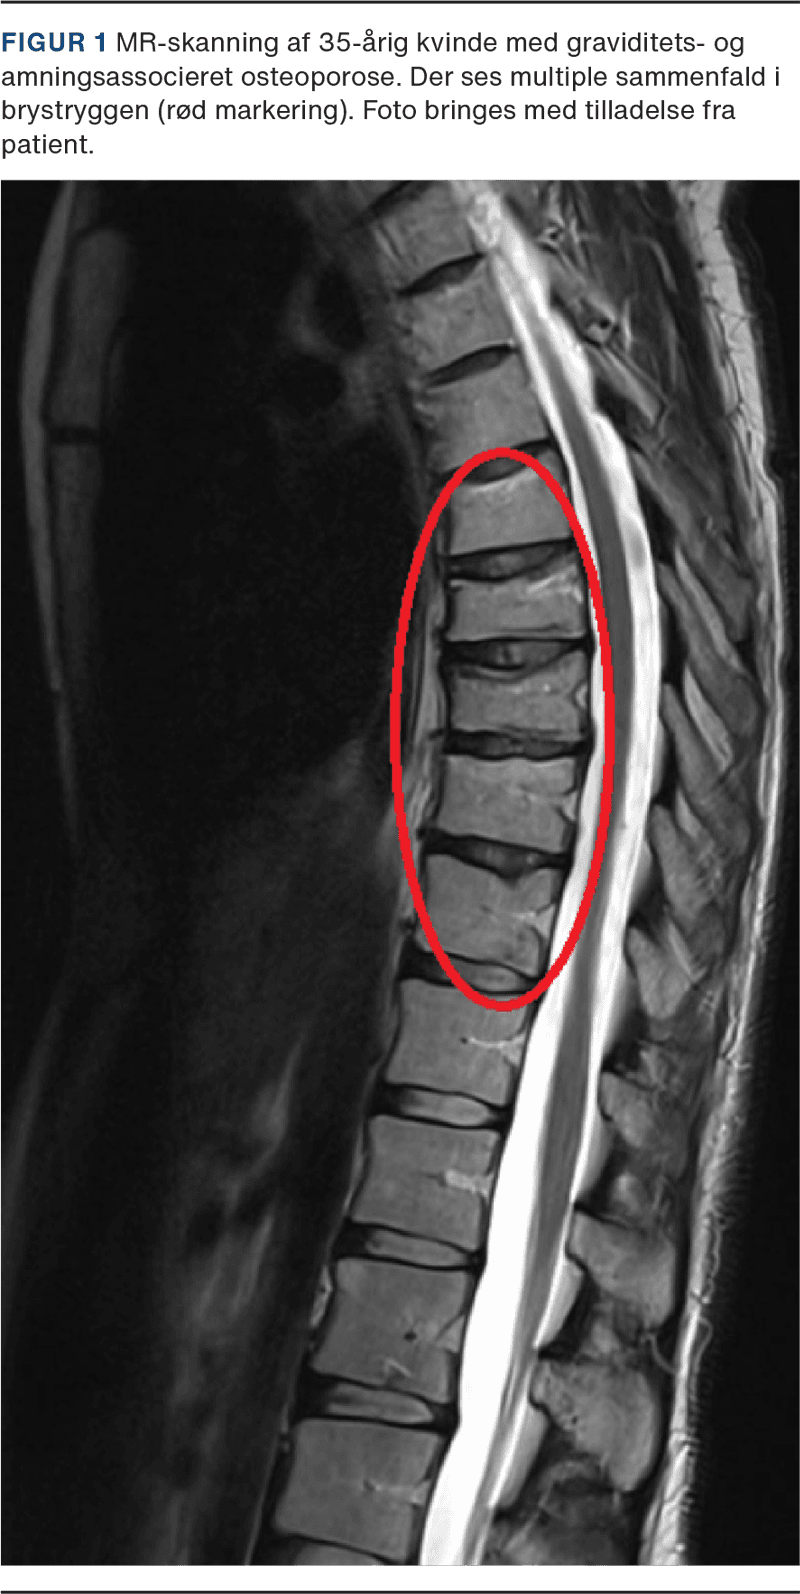

Som ved postmenopausal osteoporose er det frakturerne, som giver symptomer ved GAO. Spontane eller lavenergifrakturer forekommer primært i columna, se Figur 1, og langt mere sjældent andre steder. Samlet ses 90% af de vertebrale frakturer i tredje trimester og op til tre måneder post partum [11]. Af alle vertebrale frakturer opstår 20% under graviditet og 80% i ammeperioden [3], og de præsenterer sig helt overvejende som akut indsættende kraftige lokaliserede smerter i columna > 90% [3]. Højdetab og øget torakal kyfosering ses klinisk [3, 17]. Den gennemsnitlige alder er i en nylig metaanalyse fundet til 34,2 år [3]. I et followup-studie af vertebrale frakturer med 107 kvinder [9] rapporterede de fleste kvinder symptomdebut allerede i andet trimester. I et andet systematisk review fandt man først symptomdebut fra tredje trimester, mens den seneste symptomdebut var ni måneder post partum. Lokalisationen af frakturerne blev beskrevet i 155 tilfælde med i alt 684 vertebrale frakturer, og den gennemsnitlige affektion var 4,4 hvirvel pr. patient. Hvad angår lokalisation, var de tre hyppigst involverede vertebrae Th12, L1 og L2 (32,6% af alle frakturerne) [6].

GAO diagnosticeres typisk ved optræden af en spontan/lavenergifraktur under sidste trimester af graviditeten eller i ammeperioden samtidig med lav BMD for alder (Z-score ≤ −2) målt ved DXA [18]. Ved mistanke om sammenfald i columna rekvireres konventionel røntgen af lænde- og brystryg. Hvis mistanken opstår under graviditet, anvendes i stedet MR-skanning. I tilfælde, hvor den kliniske mistanke er meget stor, men røntgenbilledet er uden tegn på fraktur, kan suppleres med en MR-skanning. MR-skanningen har en højere sensitivitet i forhold til frakturdetektion, som muliggør vurdering af frakturens alder, og kan anvendes til at udelukke malignitet [19]. DXA udføres tidligst efter fødslen. Øvrige sygdomme, som kan medføre spontane/lavenergifrakturer, herunder malignitet, osteomalaci og monogenetiske knoglesygdomme (f.eks. osteogenesis imperfecta) bør overvejes. Klinisk og biokemisk skal undersøges for sygdomme, som kan give sekundær osteoporose.